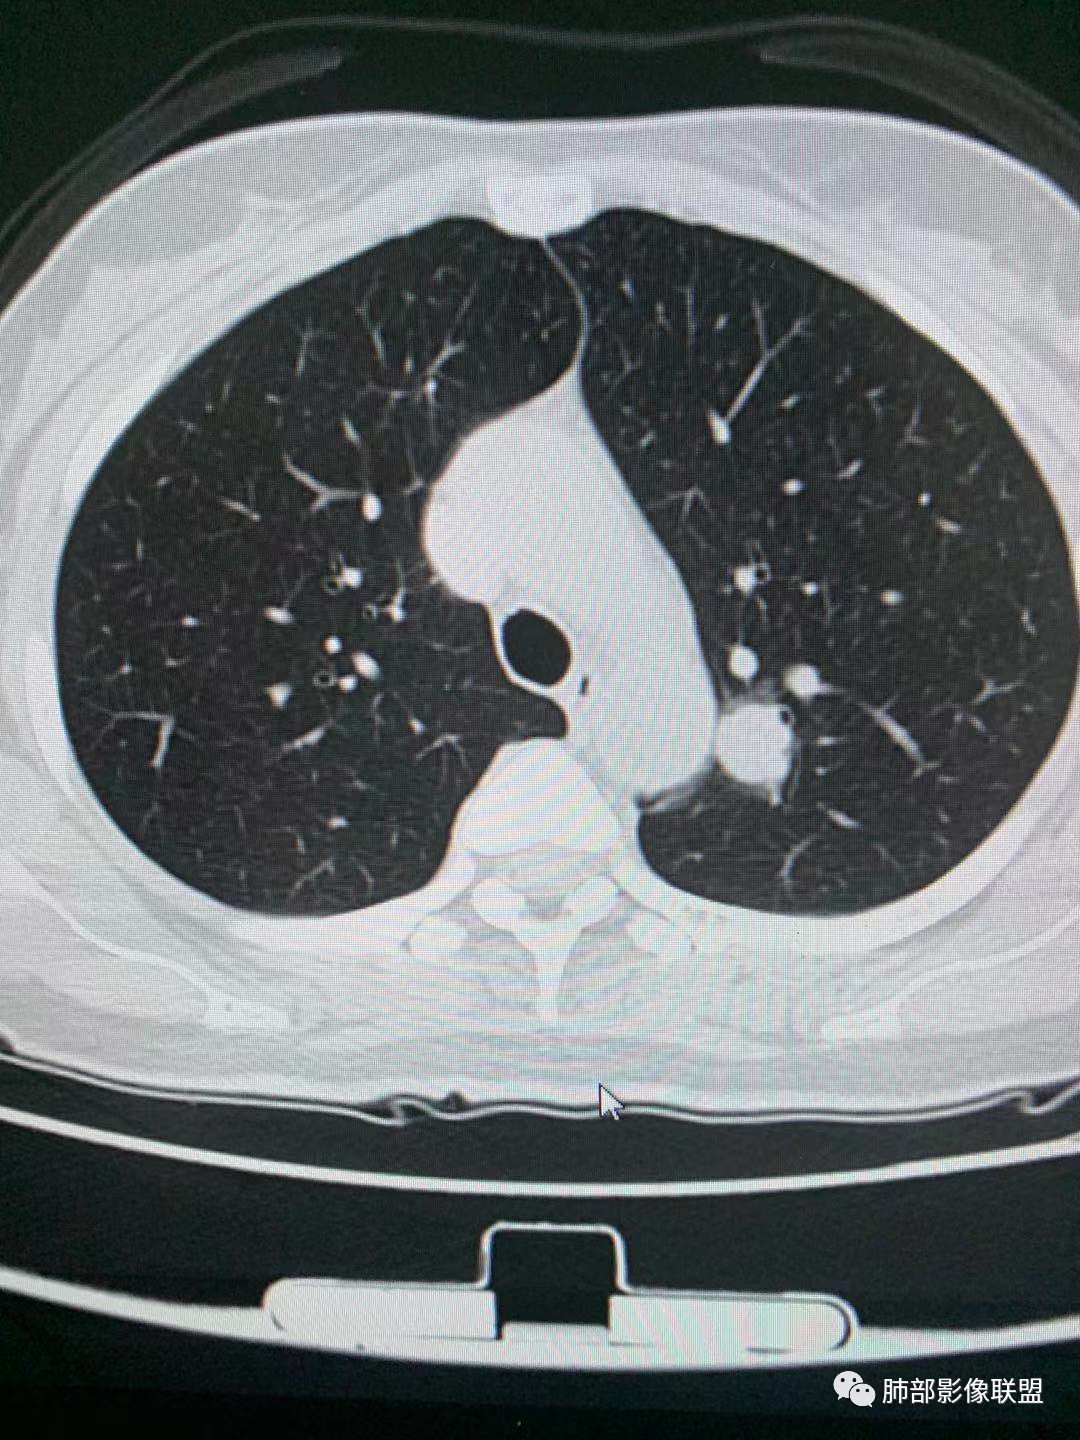

左肺上叶实性结节,光滑,支气管血管贴边,晕,强化持续。两年前就有,考虑psp。另外左肺上叶纵膈侧胸膜下及中带两处混合磨玻璃结节,考虑原位和微浸润可能,需要随访看看。

左肺上叶实性结节,边缘光滑清晰,血管贴边,渐进性延迟强化,密度均匀,考虑PSP. 医学百科网 | YxBaike.Com

贴边血管征,强化延迟,考虑PSP 医学百科网 | YxBaike.Com

左肺上叶实性结节,边缘光滑清晰,血管贴边,渐进性延迟强化,密度均匀,考虑PSP.但是强化幅度不够,需要鉴别早期肺癌

最大的靠后,有血管贴边征,渐进性明显强化,考虑PSP可能大

靠前部中等大小结节考虑MIA

靠中部最小的那个结节AAH或者慢性炎症均有可能 医学百科网 | YxBaike.Com

中年女性,左肺上叶实性圆形结节,边缘有晕,血管及支气管贴边,强化尚均匀,渐进性明显强化,考虑为PSP可能 医学百科网 | YxBaike.Com